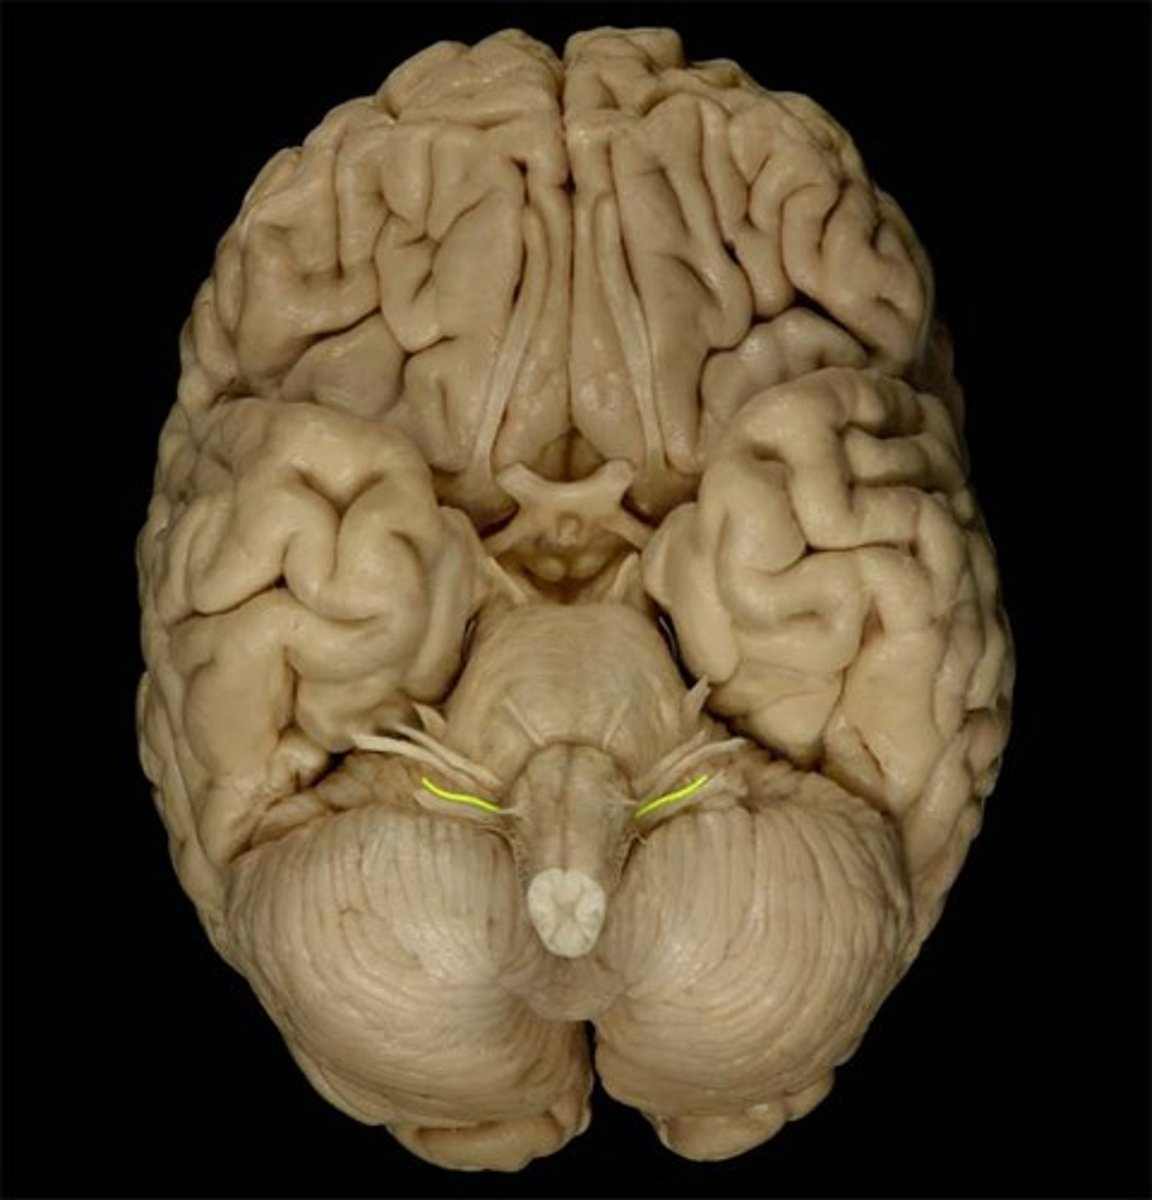

Vagus nerve (CN X)

Medulla oblongata

Glossopharyngeal nerve (CN IX)